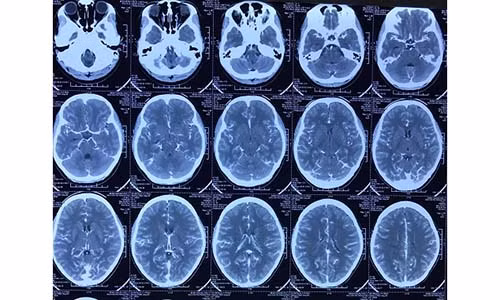

Kết quả chụp MSCT phát hiện khối dị dạng động tĩnh mạch vùng vận động gây liệt nửa người. Bệnh nhân được chỉ định mổ cấp cứu: lấy máu tụ trong não, lấy khối dị dạng mạch. Sau mổ bệnh nhân tỉnh, tự co chân tay được, còn yếu nhẹ nửa người trái. Sau 5 ngày bệnh nhân đã ra viện.

| Hình ảnh dị dạng mạch não sau phẫu thuật. |